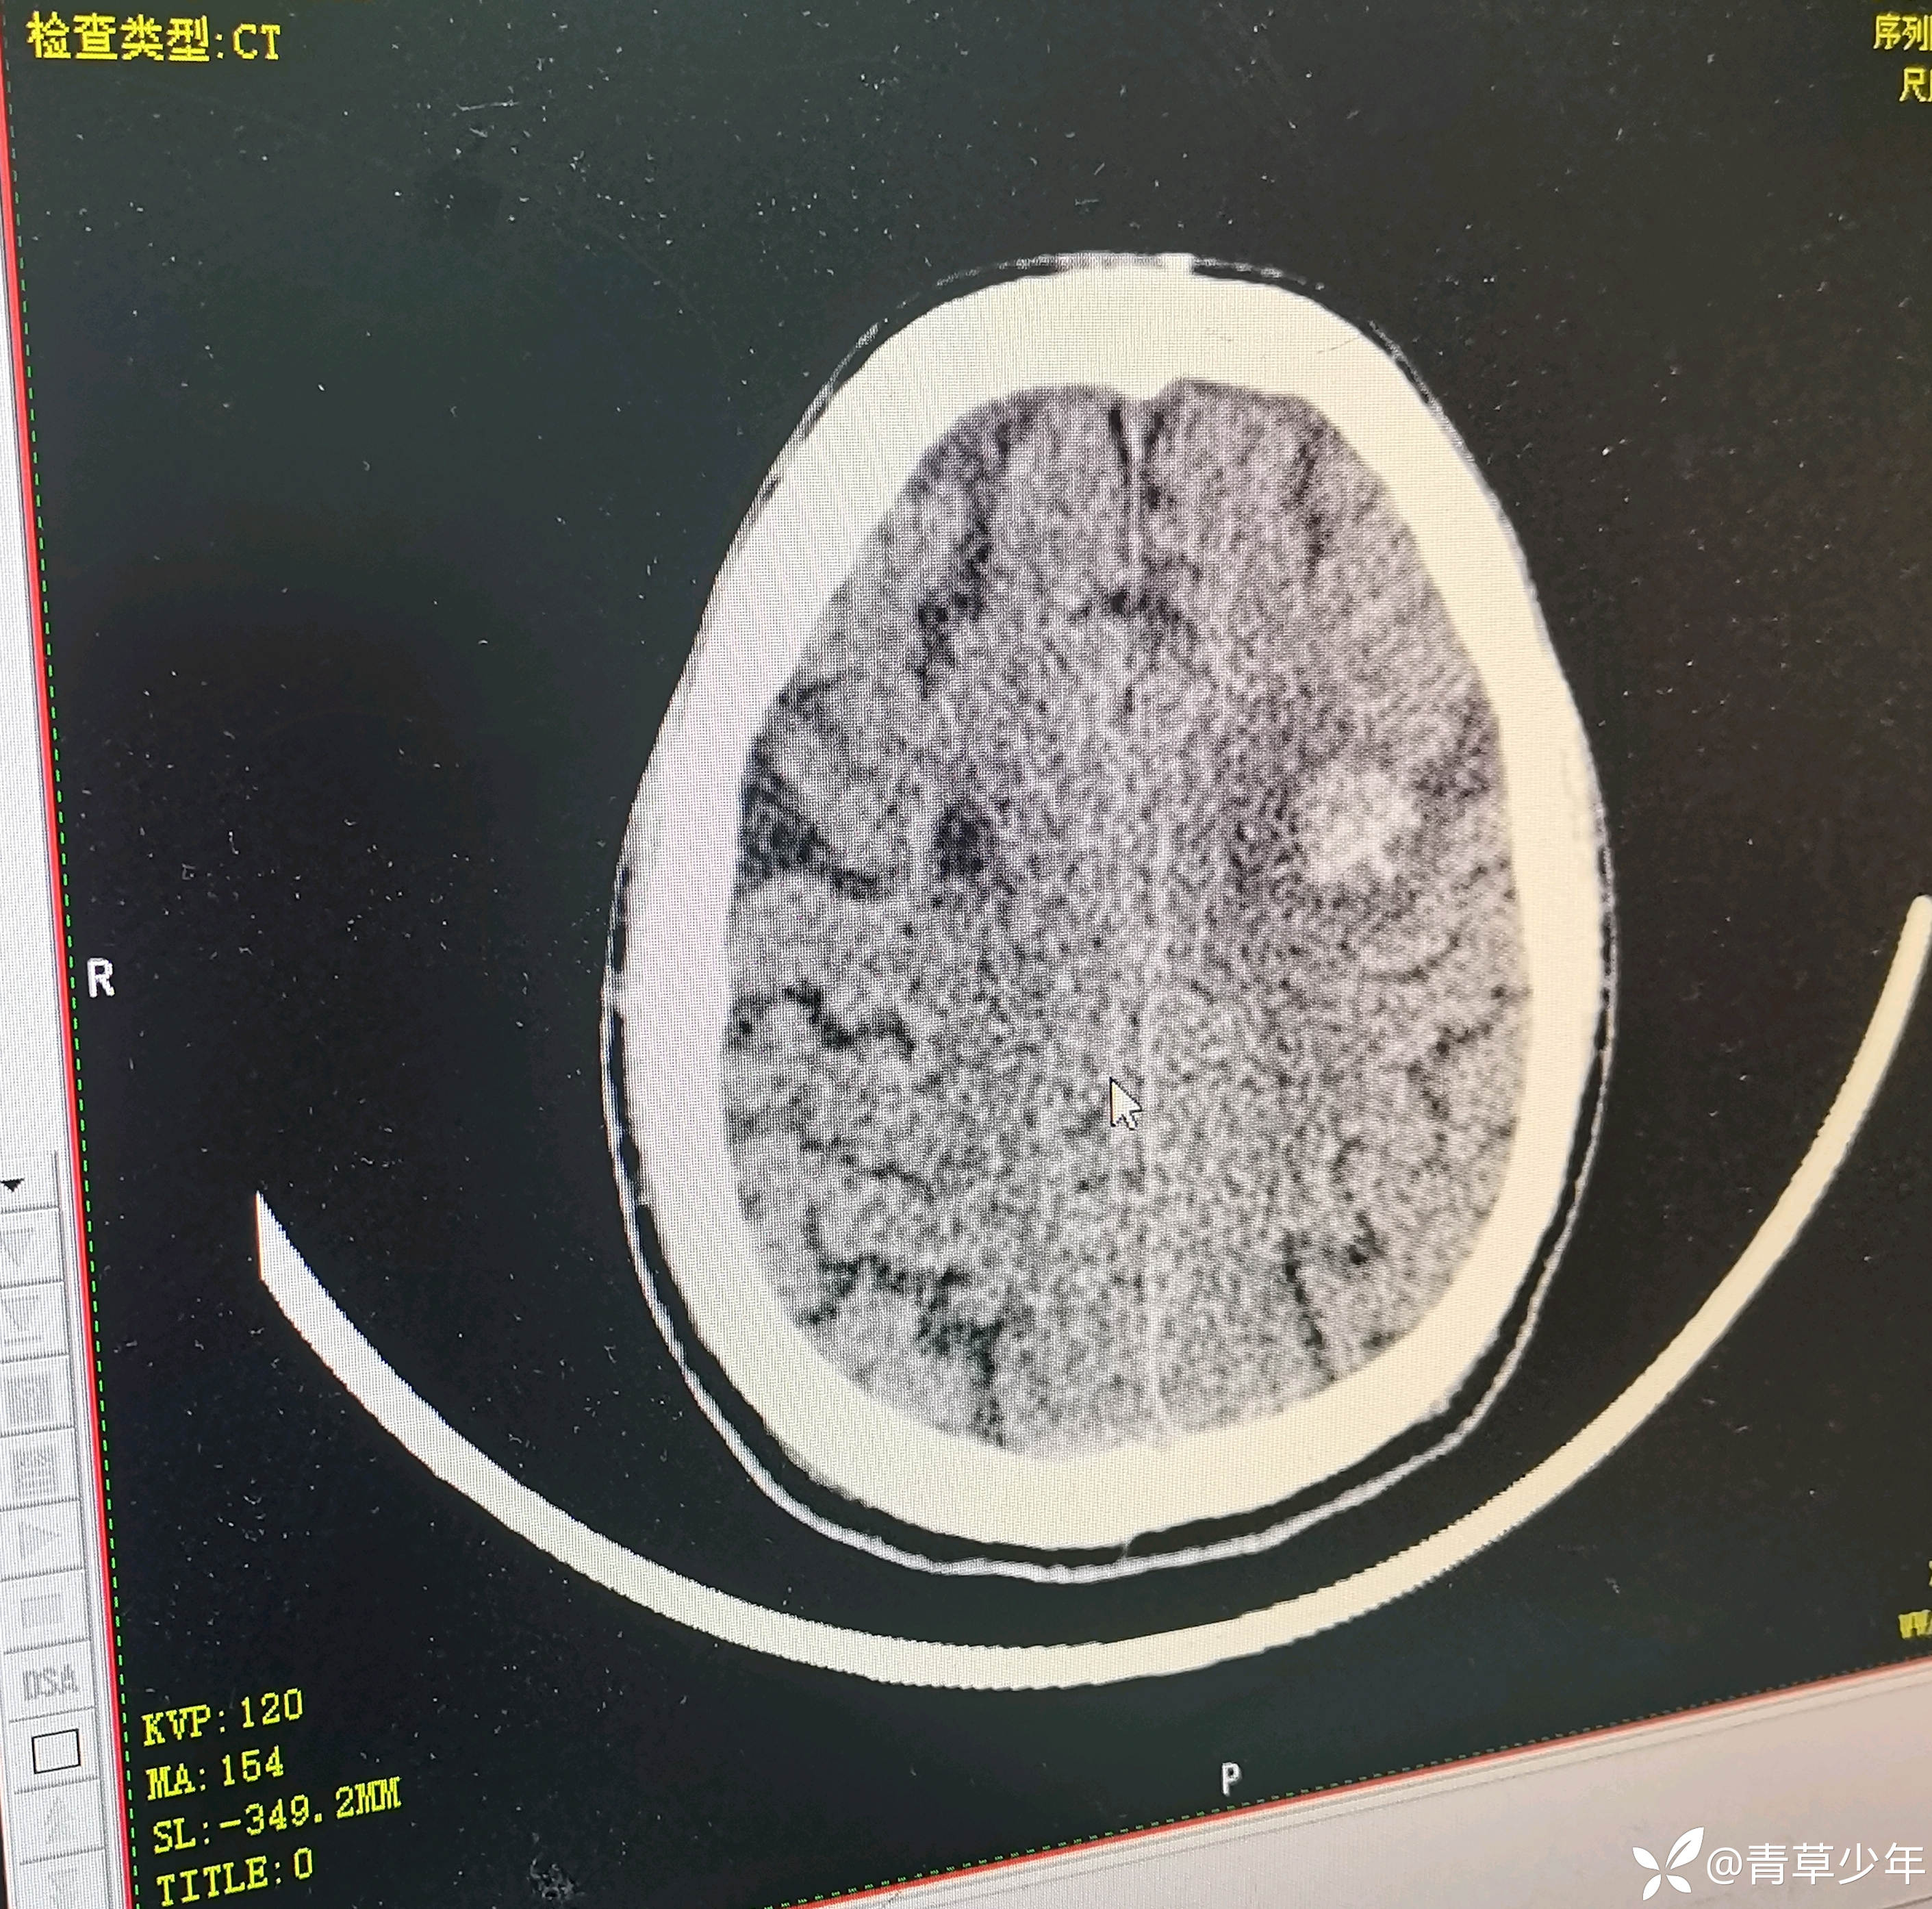

头颅CT结果示

临床诊断:1.颅内出血 2胰腺肿瘤